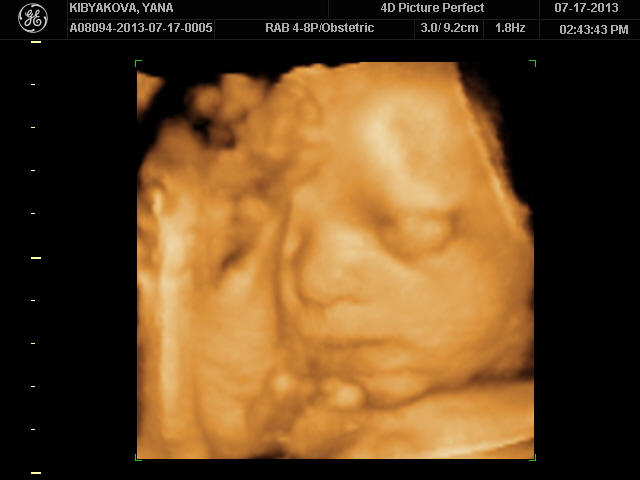

И тут я чисто случайно наткнулась на рекламу УЗИ 3Д/4Д, подумала что не плохо было бы позвонить и узнать хотя бы,да и ехать было недалеко совсем))А тут меня обрадовали что как раз через пару часов можно будет приехать и сделать узи в него входят 3 распечатанные фотографии вашего карапузика, видео вашего карапуза на диск и кучу фотографий на второй диск и вся эта прелесть за 79$!)))

Радовалась я своему капризному мужчине вместо 30 минут - целый час!!!)))Т.к. хорошие снимки он просто не давал сделать!Глазки мы прятали ручками и параллельно запихивали ноги себе в рот! Сына ну зачем ноги то?))))

Чего он только не делал!Там целая фото-сессия получилась у нас из 34 фотографий!

Ноги только уберет,как начинаем снимать в 4Д он их уже тут как тут возле личика держит!)Борьба была серьезная с ним))И пальцы рук в рот пихает или рот вообще открыт - как у папы!)Ноги выше головы - и куда он их так задрал!?Место у него для них ещё есть))Обитает он вниз головой,но строго с правой стороны и где голова там и ноги с руками))

Спорили после с мужем на кого он похож!Мои родители в голос закричали что он моя копия,кроме глаз, муж говорит что нос его и верхняя губа тоже,а нижняя моя!))Я не стала ни с кем спорить просто весь день перекручиваю подробности узи)Моя кроха даже улыбаться умеет и хмуриться - это мы тоже увидели,жаль заснять не успели...В общем я со своих эмоций уже всего и не вспомню, но знаю точно что это было пока что самое лучше свидание с ним!)

И ножку показали всем!Вот какая большая у нас она))))Самое главное что муж разглядел ВСЁ(я думала придется объяснять ему что где) и так же в него влюблен ещё больше как и я!))))Я теперь вообще не отпускаю фотки эти))Постоянно смотрю своего Сашульку